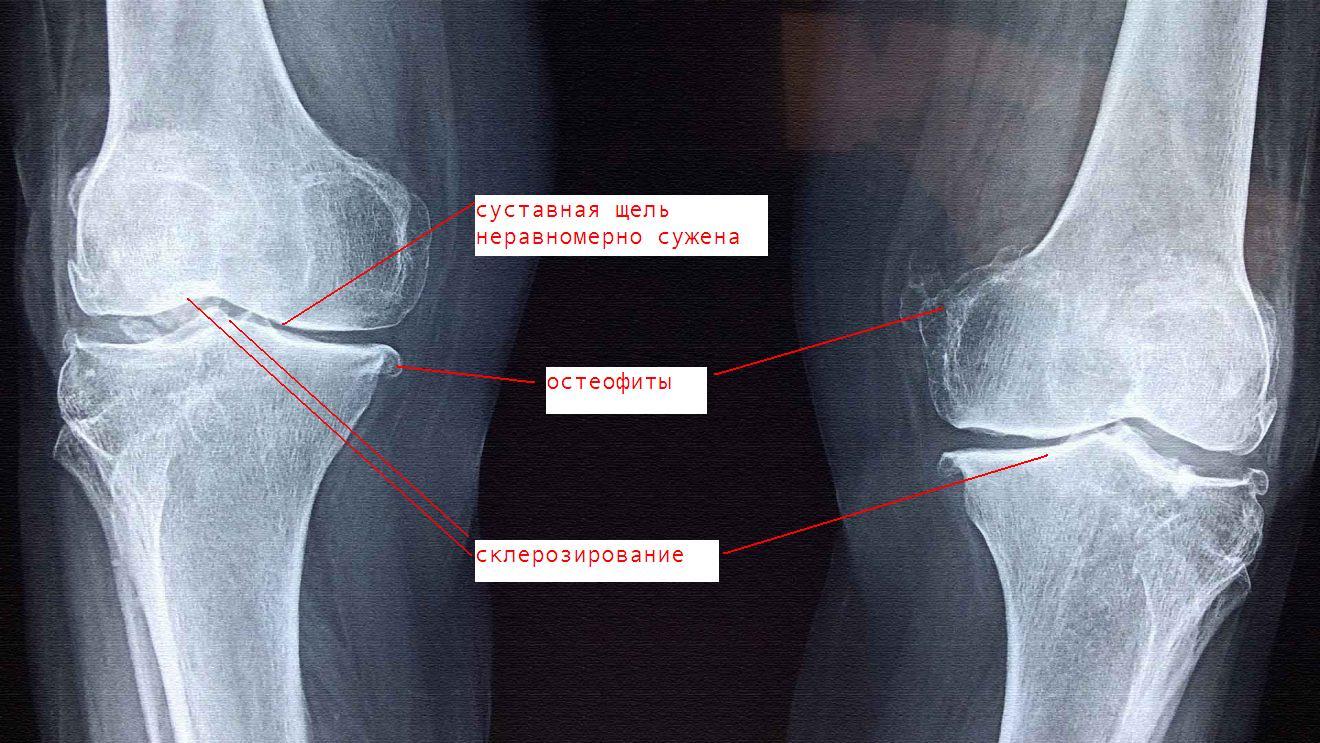

Рекурвация коленного сустава: рентгеновские снимки и объяснения